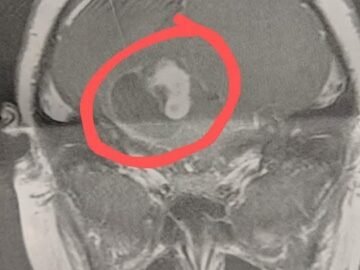

In December 2020, I took my 9-year-old son for his yearly physical. We had no concerns and expected to be in and out in less...